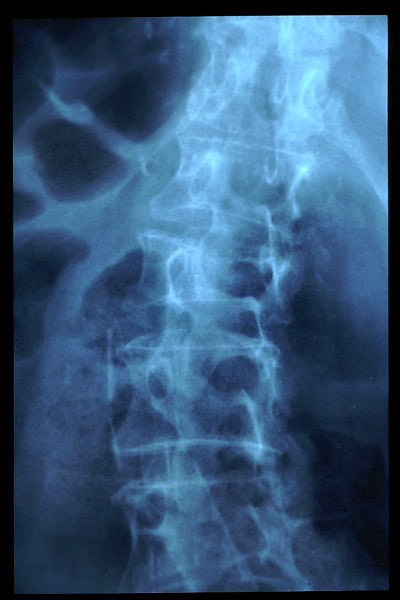

Osteoporosis. Cifosis.

Escoliosis, artrosis, aplastamiento...